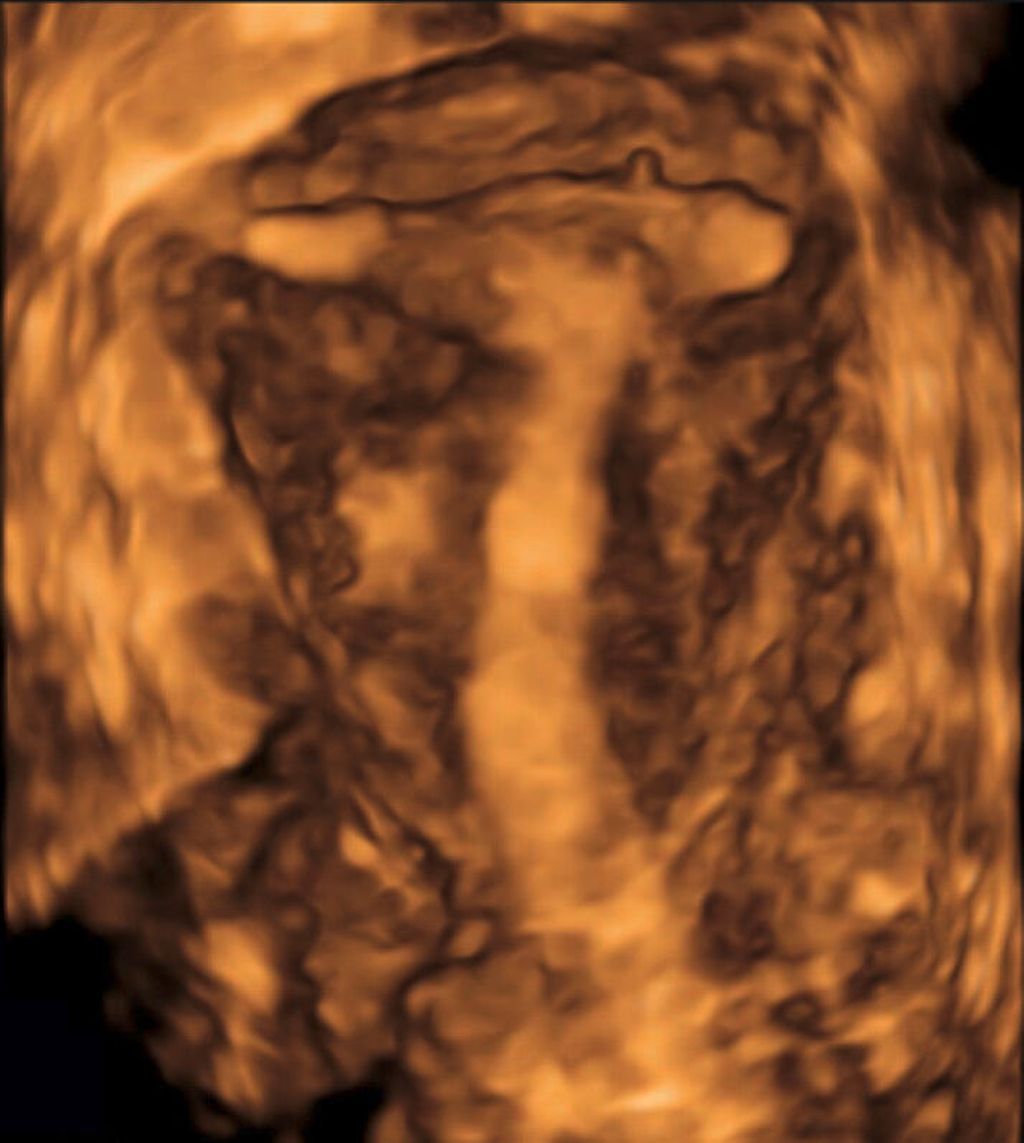

Die Untersuchung wird idealerweise bei hoch aufgebautem Endometrium durchgeführt. Nach Erstellung der Koronarebene kann sowohl die äussere als auch die innere Uteruskontur dargestellt und die Fundusdicke («fundal thickness», FTH) bestimmt werden (Abb. 2). Eine allfällige Septierung ist dabei einfach erkennbar und mittels eines Messkreuzes leicht objektivierbar. Dies lässt sich einfach konstruieren: Zunächst wird eine Hilfslinie zwischen den beiden inneren Tubenostien eingezeichnet (sog. Interostiallinie). Nun kann kranial davon die Fundusdicke (bis zur Serosa) und kaudal davon die Länge des Septums sowie der Winkel der Septumspitze bzw. Carina ausgemessen werden (Abb. 3). Je nach Klassifikationssystem unterscheiden sich hier die Definitionen bzw. Massangaben, welche zur Diagnose einer Fehlbildung nötig sind. Während die ESHRE-ESGE-Guideline relativ «laxe» Kriterien vorschlägt, unter deren Anwendung viele Patientinnen die Diagnose eines Uterus (sub-)septus erhalten würden (bis zu 80%!), landen gemäss ASRM-Klassifikation viele Patientinnen in einer «Grauzone». Hier bewähren sich die CUME-Kriterien, mit deren Hilfe eine Einteilung gelingt, die am ehesten der tatsächlichen Prävalenz entspricht, und dies bei entsprechender Trennschärfe.8 Die vorgeschlagenen Kriterien zur Diagnose eines Uterusseptums sind eine Septumlänge von mindestens 10 mm, ein Winkel von <140° und ein Verhältnis Septum:Fundusdicke von >110% (Abb. 4, Tab. 1).

Abb. 3: Ausmessen der Septumlänge. Nach Anlegen der Interostiallinie (grau) zwischen den Tubenostien können die Fundusdicke und das Septum (innere Einkerbung, engl. «indentation») ausgemessen werden. Nicht eingezeichnet ist hier die Messung des Septumwinkels

Endometrioseknoten, etwa in der Blase, können anschaulich dreidimensional dargestellt werden im Sinne einer «virtuellen Zystoskopie» (Abb. 10). Auch Visualisierungen von Herden im Rektosigmoid (Abb. 11) stimmen gut mit den intraoperativen Befunden überein, wobei hier die 2D-Sonografie zur genauen Lokalisation und Grössenausmessung sicher im Vordergrund steht.